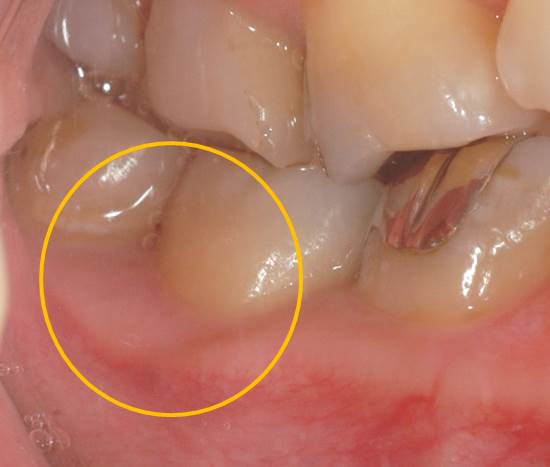

今回は、限局した部分に重度歯周炎が認められたケースです・

○で囲んだ部分に深い歯周ポケット(9mm)があります。